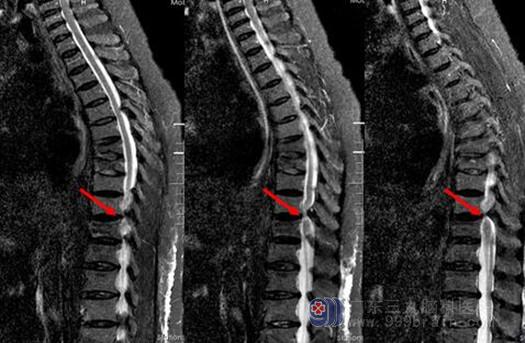

黄韧带骨化核磁和CT图像

黄韧带骨化核磁